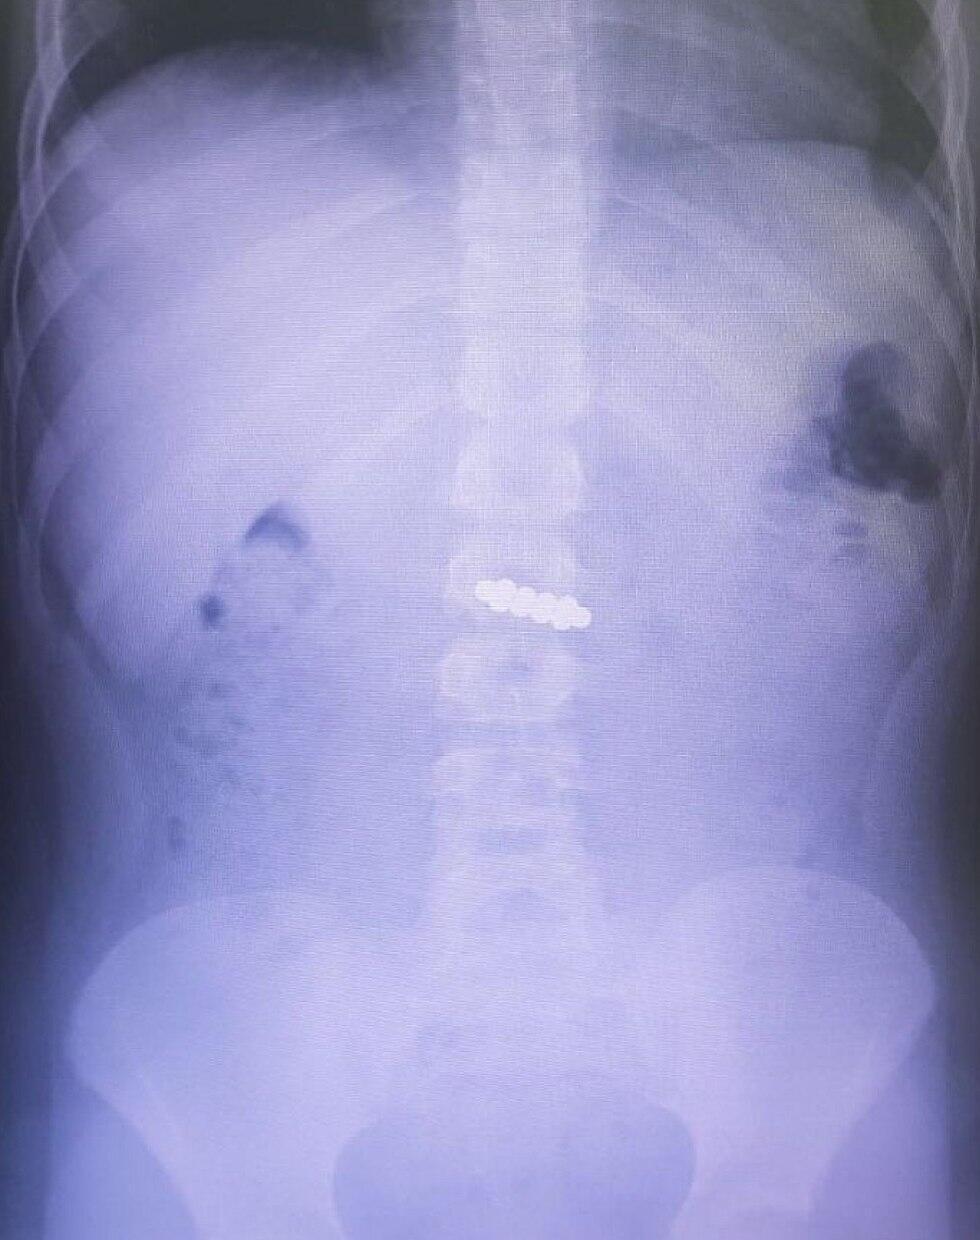

"Мы срочно сделали ребенку рентгенографию и обнаружили, что магнитная цепочка находится в желудке", - рассказала детский гастроэнтеролог доктор Ханни Таф.

Опасность заключалась в том, что магниты могли слипнуться и привести к кишечной непроходимости или перфорации желудка или кишечника. Поэтому мальчика срочно отправили в операционную, где под общей анестезией достали магниты из органов пищеварения.

Для этого хирурги использовали специальное эндоскопическое оборудование, которое позволило извлечь предметы одной цепочкой.